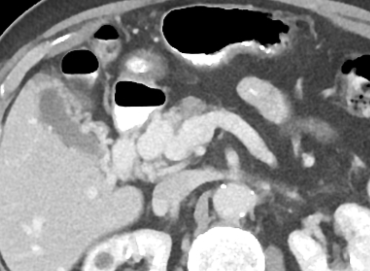

- Sur thrombose porte chronique ++

- Voie de dérivation Porto-Porte (contrairement à porto-systémique du reste de l’hypertension portale)

- Péri-veine porte et Lit vésiculaire ++

- Le Cavernome se développera surtout sur un foie sain avec occlusion porte rapide

Biliopathie portale

- La dilatation des petites veinules péri-biliaires peut compresser les voies biliaires (sorte de Mirizzi) → Biliopathie portale = dilatation souvent asymptomatique des VB